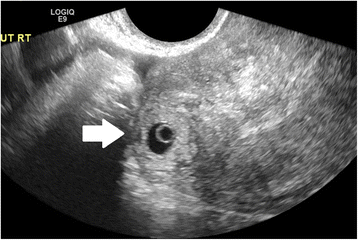

In women presenting with bleeding or pain, pregnancy location is often not definitively visualized on the initial ultrasound at presentation; however, diagnosis of EP by ultrasound is possible when following careful guidelines. Identification of a gestational sac and fetal pole, with or without cardiac activity, or a hyperechoic ring—called the ‘bagel’ or ‘tubal’ sign (Fig. 1)—with circumferential Doppler flow (Fig. 2) is highly suggestive of an ectopic pregnancy [95, 96]. If a suspicious mass moves separately from the ovary—called the ‘blob’ sign - the positive predictive value is above 90 % in a symptomatic woman with a positive serum b-hCG and no IUP on transvaginal ultrasound [97, 98].

Interstitial ectopic pregnancy by transvaginal ultrasound. The arrow indicates thin (<5 mm) myometrium overlying the ectopic pregnancy. This finding by ultrasound, in combination with the lateral location of the gestation, has a reported specificity of 88-93 % but a sensitivity of just 40 % [101].